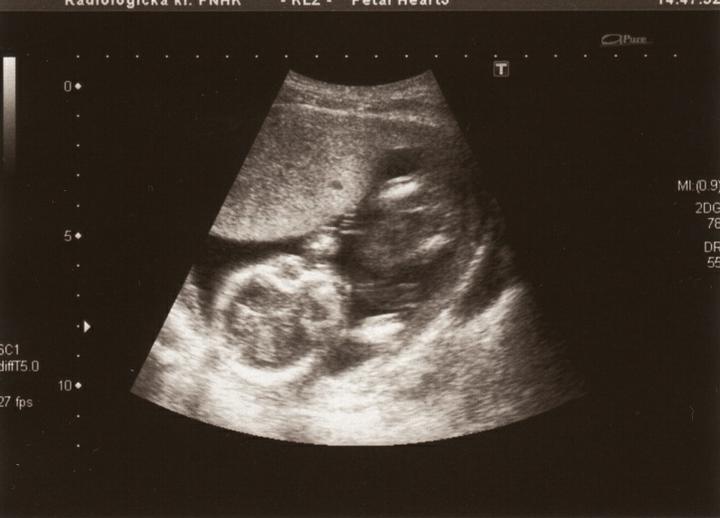

17.1.2011 UTZ ve 20tt :o)) uvidíme, zda se pohlaví potvrdí :o)

čekáme holčičku :o)